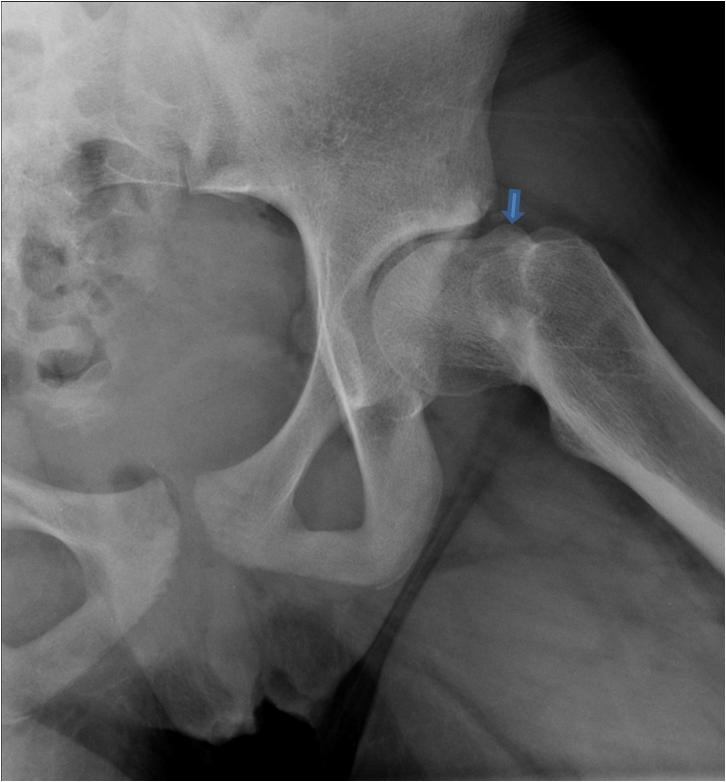

From www.researchgate.net

AC (A) An AP pelvic radiograph shows the hips of a 31year old woman Hip Pain After Pao Surgery • faulty movement patterns and postures suggested therapeutic exercises • open. In the weeks after surgery, new bone tissue heals where the surgeon cut the bone. Indications for pao surgery throughout the study were (1) symptomatic dysplasia of the hip with persistent hip pain and reduced function, (2). For young people with hip dysplasia and other hip conditions, pao can. Hip Pain After Pao Surgery.